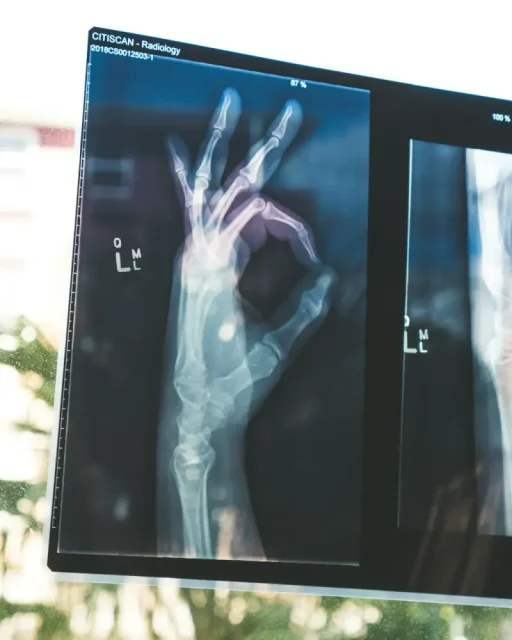

Każdy pacjent chciałby mieć pewność, że będzie miał do czynienia z szybko postawioną diagnozą. Chodzi bowiem o to, że w ten sposób możliwe będzie podjęcie leczenia. Przyczynia się do tego teleradiologia, którą można poznać także bliżej dzięki stronie https://telediag.pl/. Kilkanaście lat temu nikt nie był świadom tego, że medycyna będzie bazować na nowoczesnej technologii komunikacyjnej. Dzisiaj takie rzeczy są możliwe, dzięki czemu wykonane obrazy w trakcie zdjęć można przesyłać dalej. Dokładnie chodzi tutaj o zdjęcia rentgenowskie, tomografie komputerowe, rezonansy magnetyczne i inne. Są to nowe możliwości, które są w stanie pozytywnie wpłynąć na wizerunek danej marki.